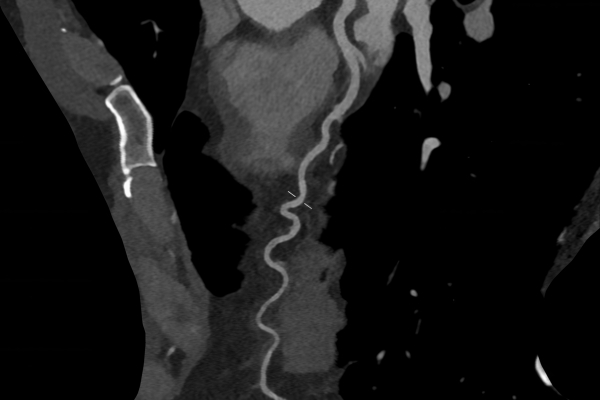

CT Untersuchung Bild

• Gefäßdiagnostik (CT-Angiographie)

Wir bieten ein breites Spektrum an Untersuchungen an, von Standarduntersuchungen der Gelenke, Organe oder großflächigen Körperregionen bis zu Spezialuntersuchungen zum Beispiel des Herzen oder der Gefäße. Zusätzlich werden Angiographien (Darstellung von Blutgefäßen), Endometriose-Abklärungen und Mamma-Untersuchungen durchgeführt. Genauere Details können Sie der MRT/CT-Übersicht und der Preisliste entnehmen, oder Sie wenden sich direkt an unser Team, das Sie gerne zur passenden Untersuchung berät.